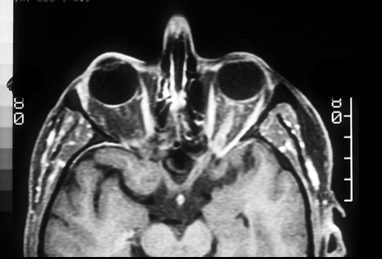

demyelinating plaque that is affecting the optic tract

damage to meyer’s loop in temporal fibers

this shows damage to meyer’s loop in temporal lobe usually caused by a tumor or stroke